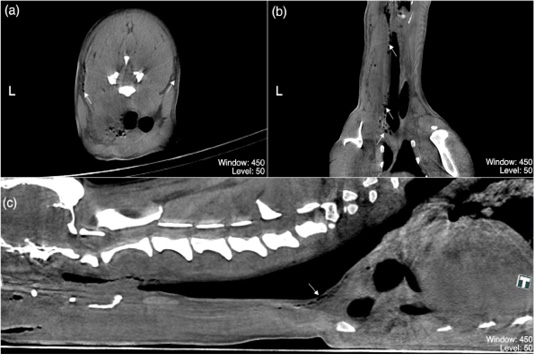

(a–c) are post-contrast multiplanar reformation (MPR) acquisitions of the neck region of the dog in present case study representing (a) transverse plane at the level of C5, (b) dorsal and (c) sagittal planes. Multiple small rounded gas-attenuating densities coalescing to form linear gas–attenuating densities peripheral to the fascial planes, oesophagus, and trachea (white arrows); indicating cervical soft tissues emphysema. Any piece of wood or splinter resembling structures were not identified from these CT acquisitions. (Window: 450; Level: 50)